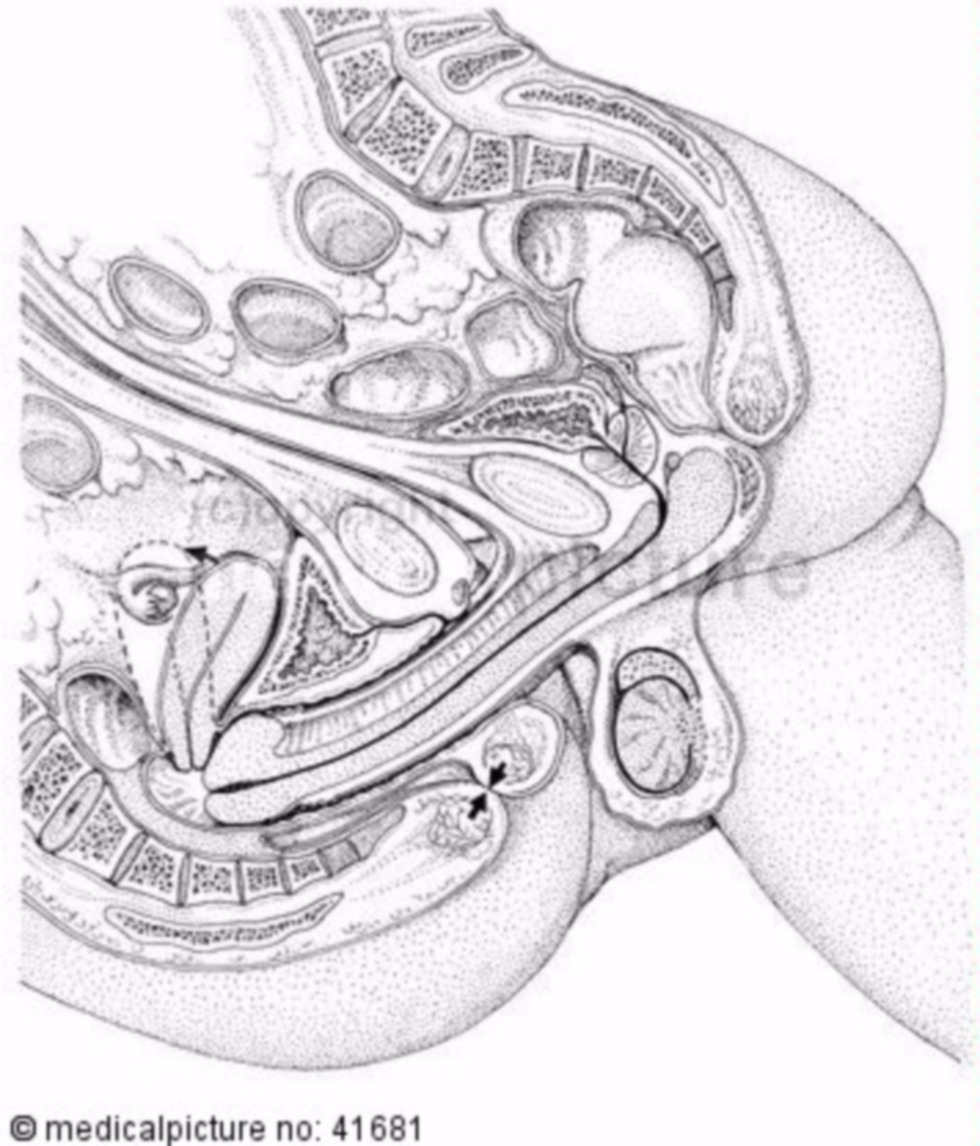

Anatomy of sexual intercourse

Anatomy of sexual intercourse in the section